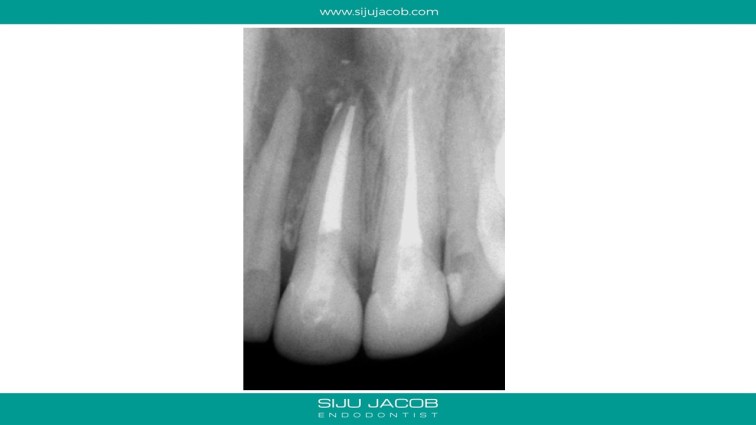

This patient had a large lesion in the right maxillary anterior region. The lateral Incisor tested vital. I decided to re-treat only the central Incisor. Despite several calcium hydroxide changes spread over 2 months, there was persistent drainage of pus. Instead of opting for the more radical option of endo on the lateral and immediate surgery, we decided to do decompression. The drainage stopped and the tooth was subsequently obturated. Patient recently came for some other work and I took a 5-year recall raiograph. It seems to be holding on for now. I was tempted to do the endo on the lateral on several occasions, but it always tests vital.